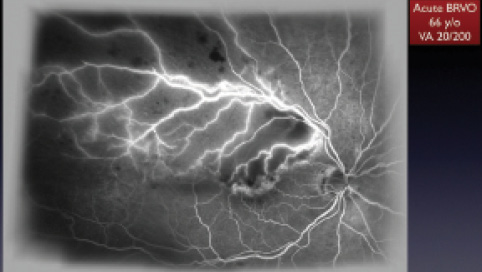

Figure 2. A 66-year-old patient with acute BRVO in the right eye; FA shows capillary closure.

Figure 3. Same patient as seen in Figure 2. OCT shows cystoid macular edema. Visual acuity is 20/200.